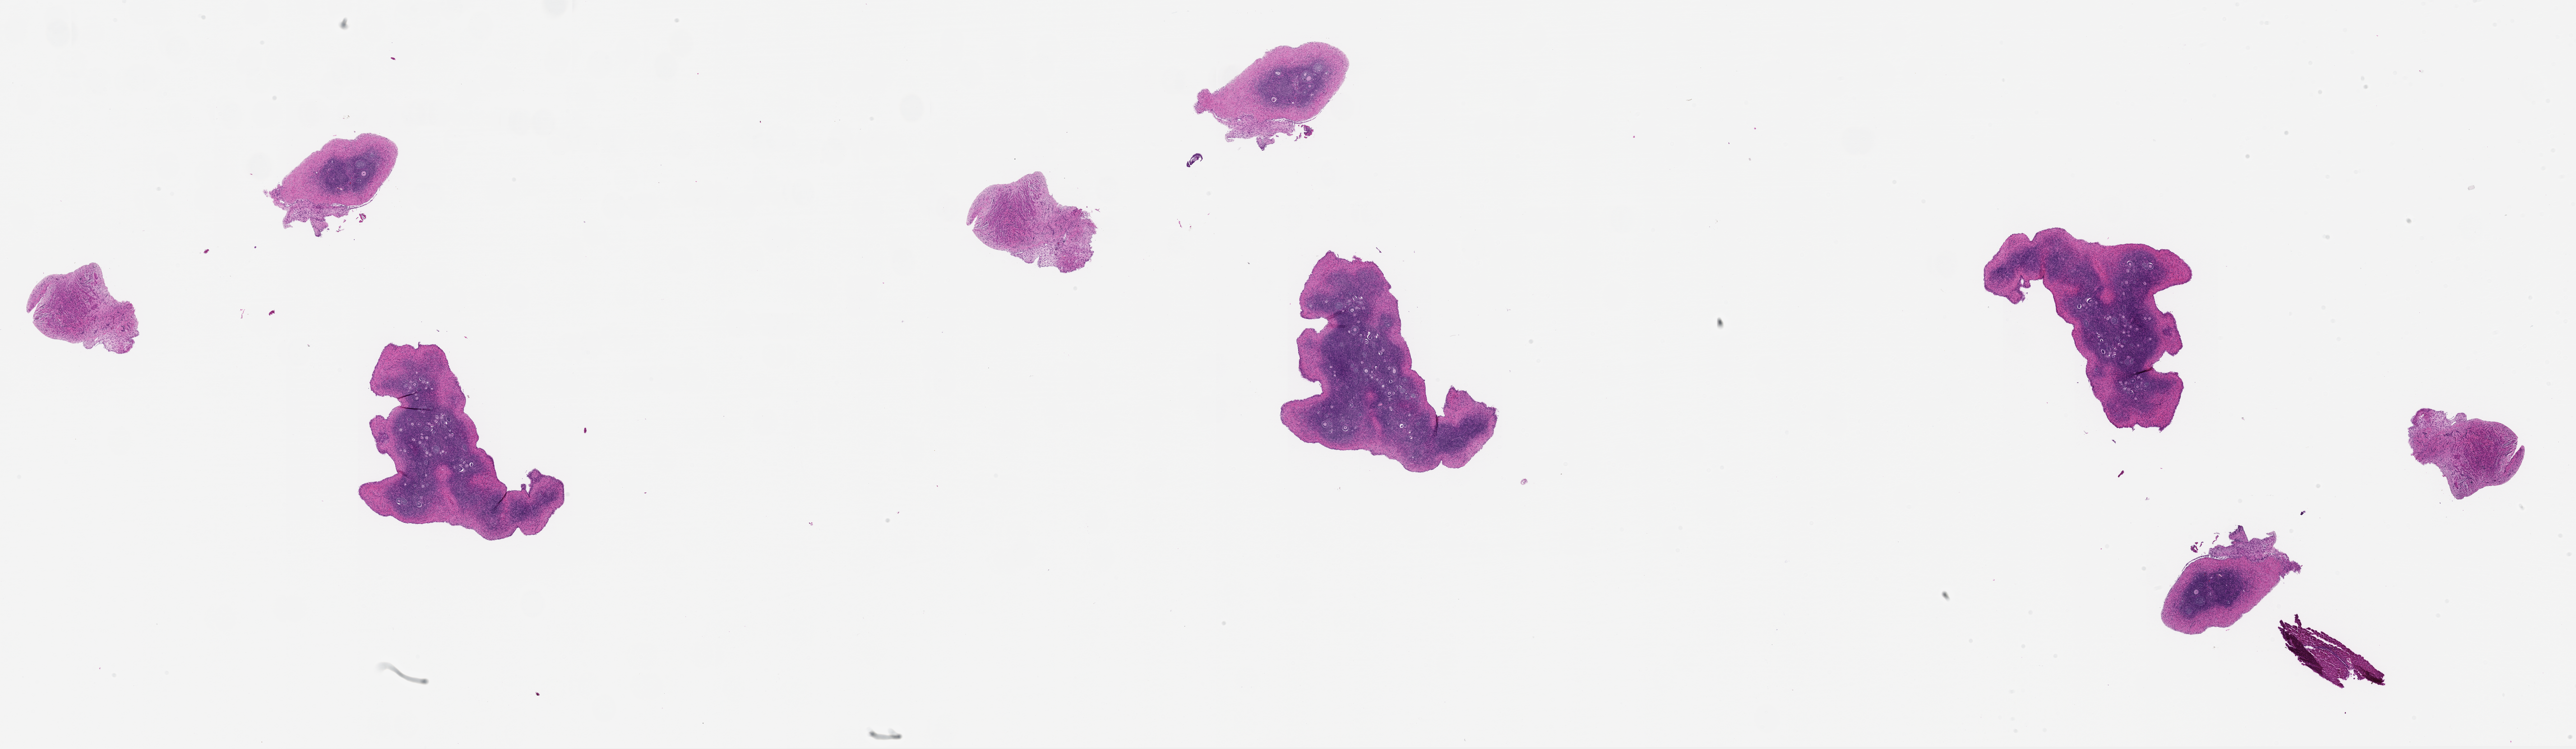

M. Zelinski, 2026, 'Zelinski Lab: Papio hamadryas Donor MZ_PH_39214 Ovary Left Slide 1', https://mother-db.org/MDB0000563, Multispecies Ovary Tissue Histology Electronic Repository, Retrieved: February 17, 2026

Genus: Papio (baboons)

Species: Papio hamadryas (hamadryas baboon)

Donor ID: MZ_PH_39214

Life Stage: adult

Age: 16 years, days

Stage of Cycle: unspecified

Accession #: MDB0000563

Ovary position: left

Location: wholeOvary

Section thickness: 5 microns

Fixation: paraformaldehyde4

Stain: hematoxylinAndEosin

Immunohistochemistry: None

Experimental treatment: None

Other pathology: None